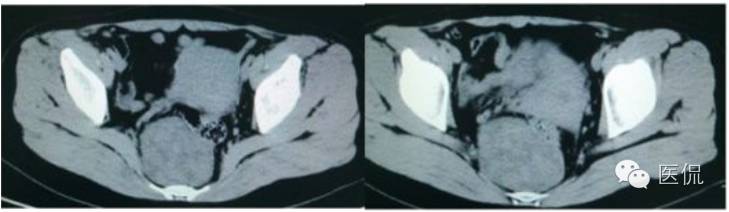

CT平扫(CT值23HU)

增强动脉期(CT值31HU)